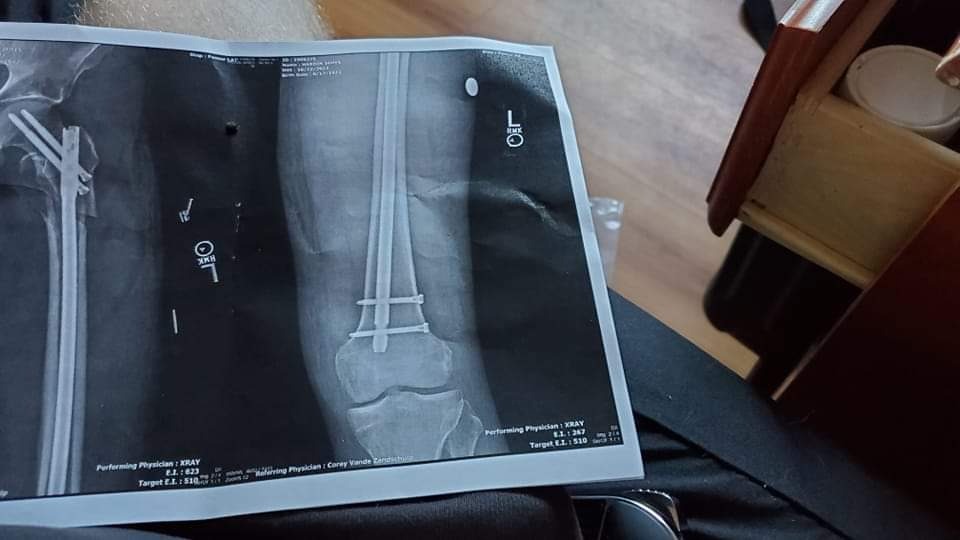

Our move out day arrives and at about 5:15pm the landlord shows up with his 2 cohorts harassing us and literally making it next to impossible to be out of the duplex by 6pm. A little after 6pm I go to close the door on the uhaul truck and I fall off the back deck of the moving truck, shattering my left femur and the landlord walks across the street without calling the paramedics. Larry hears me yelling for help as I lay on the driveway with my left leg detached with a compound break. 82% of people who break their femur in this manner die so I feel very lucky to be alive. After a 11 hour surgery, where my surgeon installed a titanium rod in my left leg that goes from my hip joint to my knee, I spent 8 days in the hospital, not one person we knew came to see me or support us and to top it off we had no money, were homeless and Larry lived in my jeep with Pepe and Paco for 6 days at the hospital parking garage as I recover from surgery. That first night there was an attempted burglary of our moving truck but luckily Larry heard them as he was sleeping in my jeep with the boys the night of my accident in front of a friends house 2 blocks away from the duplex we lived in. Larry thwarted the thieves from taking everything we owned.